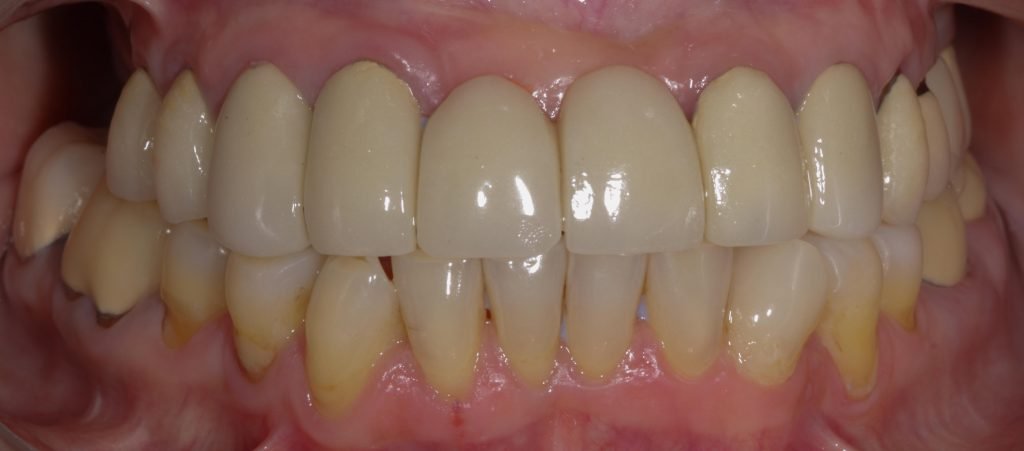

Punto Bajío Casos Clínicos Prótesis Fija sobre Implante unitario Inicio Provisional Final Prótesis Parcial Fija sobre 2 Implantes 2 Implantes Final Prótesis Bucal Removible Inicial Inicial Superior Inicial Inferior Rayos X Inicial Rayos X Inicial Frontal Final Final Superior Final Inferior Prótesis Parcial Fija/ Coronas de Circonio Sonrisa Inicial Foto Inicial Foto Inicial Inferior Foto Final Inferior Foto Final Sonrisa Final Prótesis Total Protesis Inmediatas 1 Protesis Inmediatas 2 Prótesis Removible/ Coronas Metal-Ceramica Carillas Incrustaciones Endodoncia